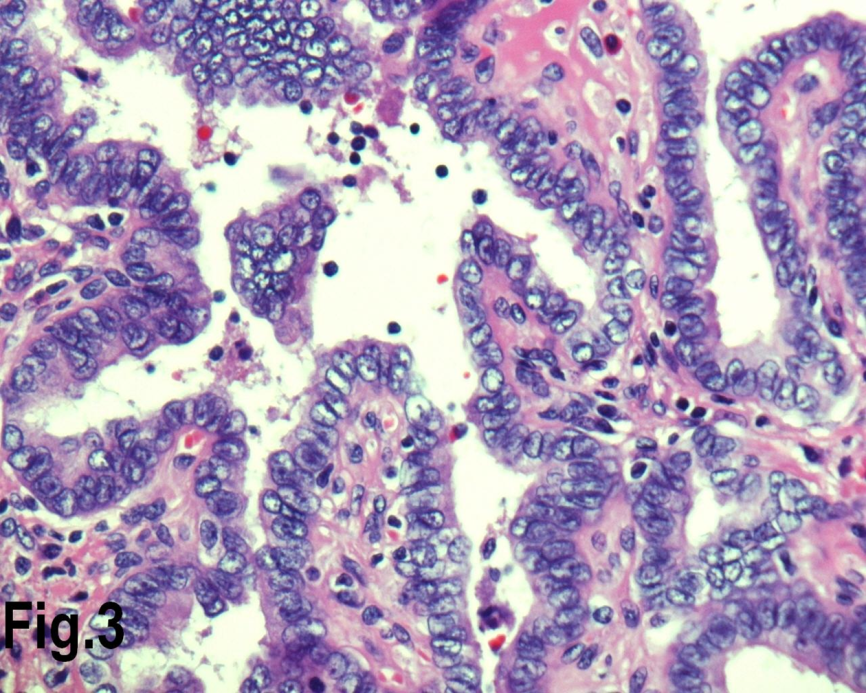

Figure 3.High power view showing follicles lined by cells with nuclear characteristics of papillary carcinoma, with prominent intra nuclear inclusions (Hematoxylin & eosin, original magnification ×400).

Solitary benign adenomas were found in 23 cases, the peak frequency was fourth and fifth decade. Female accounted for 12 cases (70.5%) for follicular adenoma (Figure 2) and 3 cases (50%) for Hurthle cell adenoma. Thyroid malignancy and it was reported in 62 cases. Papillary carcinoma (Figure 3) was the most common type of thyroid malignancy found in 44 cases (71%) followed by follicular carcinoma (9.6%) (Figure 4), medullary carcinoma (1.6) and poorly differentiated carcinoma (1.6%) (Table 3). The peak incidence for patients with thyroid malignancy in this series was third decade and male to female ratio was 3.7:1.